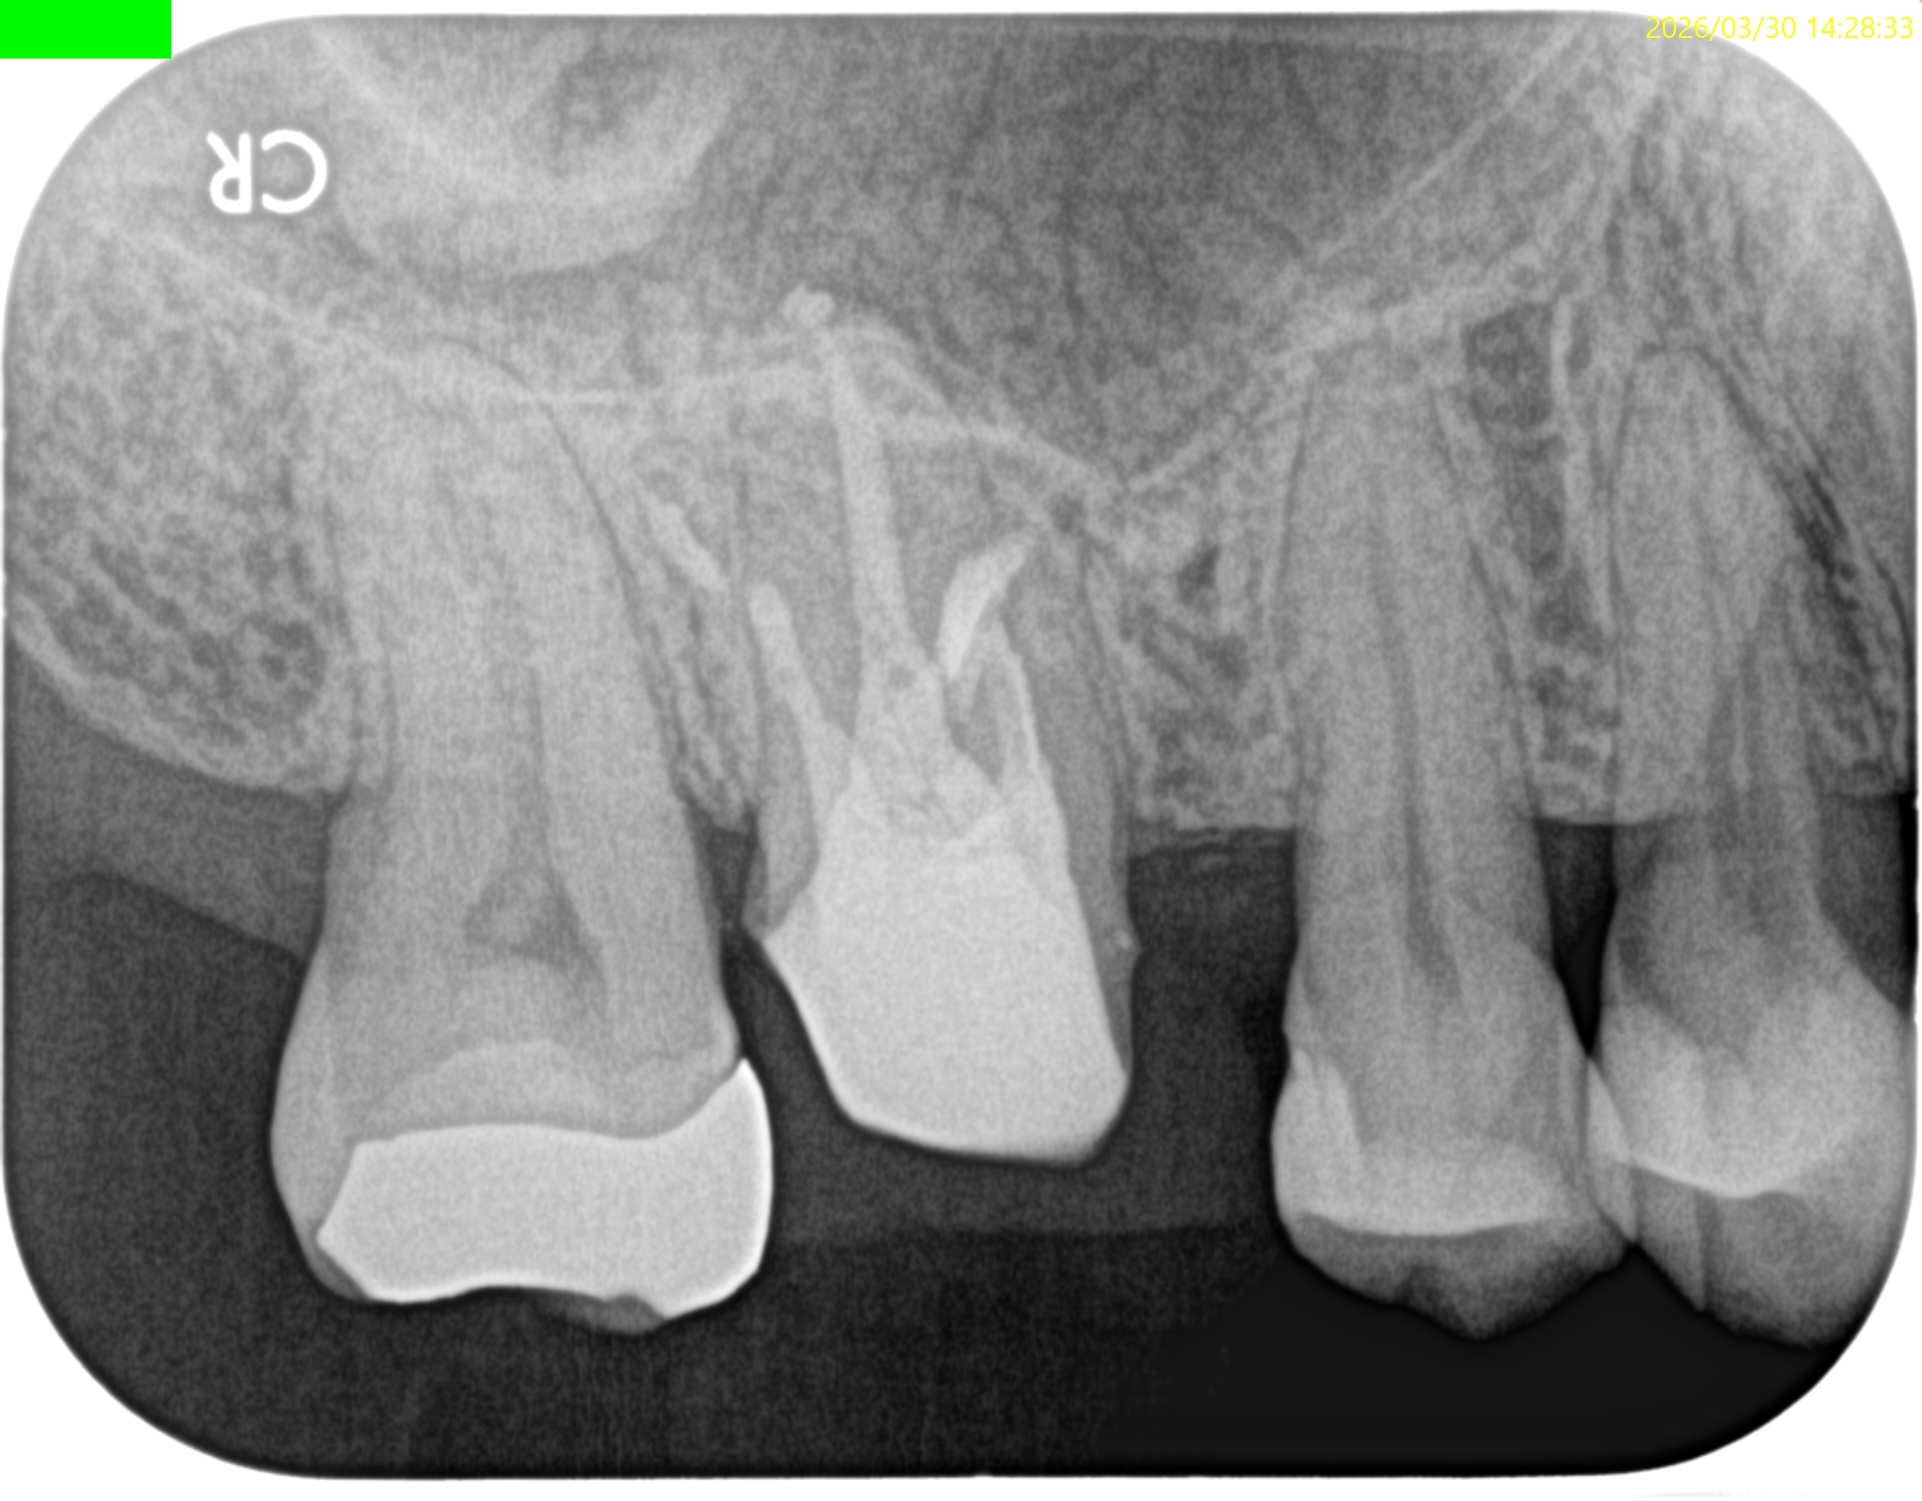

#3 MB, DB Apicoectomy 7M recall(2026.3.30)

MB

DB

P

B

7ヶ月前と比較した。

劇的に歯槽骨の開創は回復している。

そしてP根だが、根尖病変の治癒とともに口蓋側の骨欠損が大きく回復しているのがわかる。

Primary Endo Secondary Perioに見えた

のに、だ。

(歯周ポケットが正常なので歯周病ではないので上記表現は正しい表現とはいえない)

これは単純にエンドだけの問題であったのだ。

そして、

エンドの治療のみでここまで回復していることがこの歯内療法の治療のパワーを示している。

患者さんはSRPなどの歯周治療は一切していない。

HyFlex EDM #60.02でわずか数mm形成しただけなのに、ここまで歯槽骨が回復している。

ともかく、これで最終補綴もOKだ。